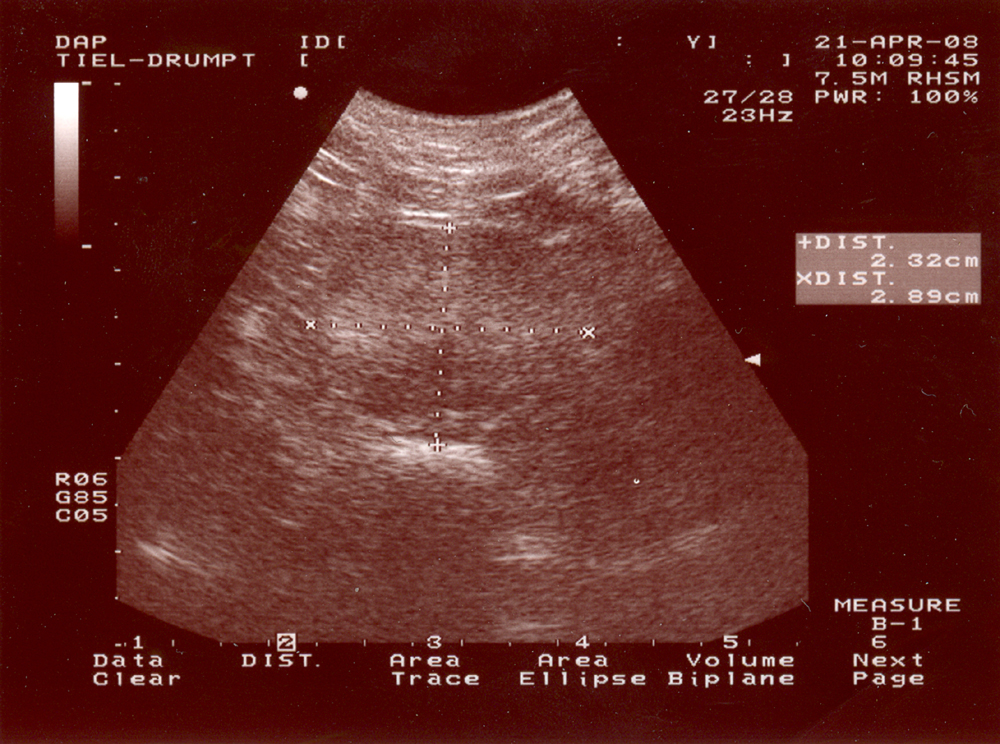

Zoals aangegeven groeit de prostaat onder invloed van testosteron. Hierdoor wordt verklaard dat bij sommige hypersexuele dieren de prostaat onevenredig groot kan worden. Meestal zien we dit bij oudere, ongecastreerde reuen. Klachten die kunnen optreden zijn bijvoorbeeld dat de hond moeilijk kan poepen of wel eens wat druppeltjes vocht verliest onafhankelijk van het plassen. Soms vertoont een dier helemaal geen klachten bij deze afwijking. In sommige gevallen kan de dierenarts de prostaat rectaal voelen en beoordelen of de prostaat inderdaad vergroot is. In andere gevallen is een echo nodig om de prostaat in beeld te brengen. Een echo geeft zowiezo meer informatie over de aard van de vergroting.

Een prostaatinfectie kan op een aantal manieren ontstaan. Omdat de blaas en prostaat door de plasbuis verbonden zijn kan een bacteriële blaasontsteking tot een prostaatinfectie leiden (andersom kan een prostaatinfectie een blaasinfectie tot gevolg hebben). Vaak is een prostaat gevoeliger voor infectie als hij al vergroot is. Als de prostaat geinfecteerd is, kan uw hond daar goed ziek van zijn. Het kan u bijvoorbeeld opvallen dat hij pijnlijk is bij het plassen. Bij een rectaal onderzoek zal het dan ook pijnlijk zijn om de prostaat aan te raken. Soms kan het nodig zijn om een echo te maken en/of wat prostaatvocht af te nemen om te kijken of er inderdaad sprake is van een ontsteking. Indien een prostaatinfectie wordt vastgesteld zal meestal met antibiotica moeten worden behandeld.

In een heel enkel geval is er sprake van kanker in de prostaat. Deze aandoening is vrijwel altijd kwaadaardig en kan erg slecht worden behandeld. Doordat het gezwel op de plasbuis kan gaan drukken kan uw hond bijvoorbeeld steeds moeilijker plassen of poepen. De diagnose wordt gesteld doordat er onder echobegeleiding een monster van de prostaat wordt afgenomen en opgestuurd voor beoordeling door een patholoog.